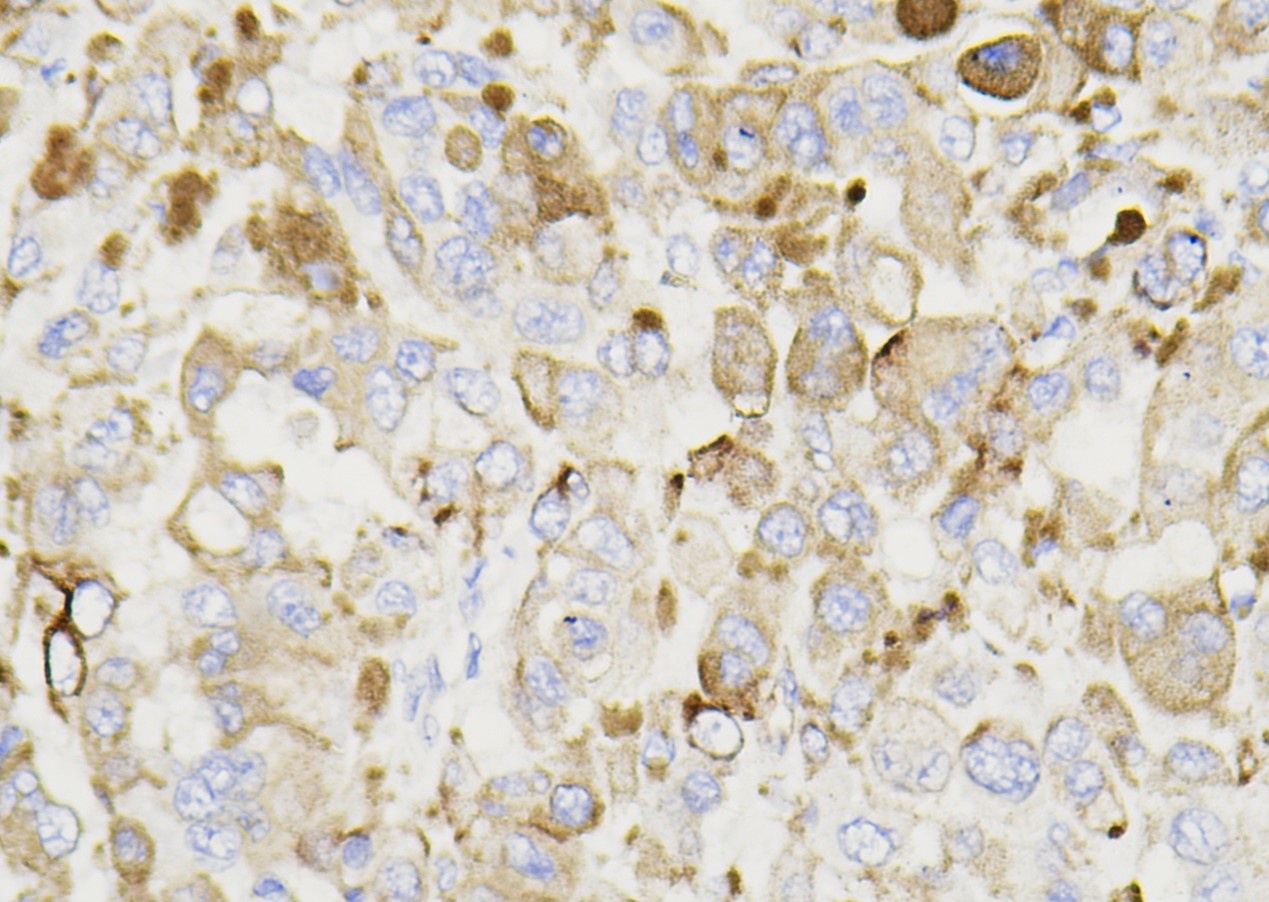

Ep-CAM

Ep-CAM(Epithelial cell adhesion molecule,上皮细胞粘附因子)由两个糖蛋白组成,表达于大多数正 常和肿瘤上皮细胞,而表皮鳞状上皮和肝细胞不表达。Ep-CAM 可用于肾嫌色细胞癌及嗜酸细胞瘤的诊断,胸腹水中腺癌及间皮细胞、间皮瘤的鉴别,卵巢浆液性癌和间皮瘤的鉴别诊断等。

| 细胞定位 | 细胞质/膜 |